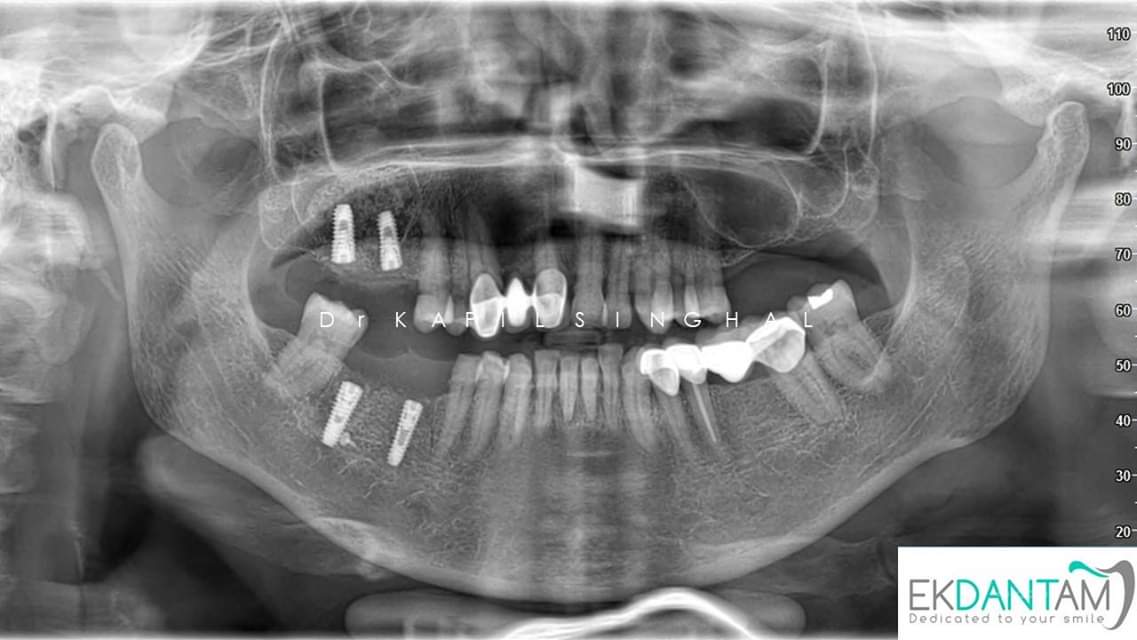

RIDGE SPLIT , GBR (GUIDED BONE REGENERATION ) & Direct sinus lift and Simultaneous Dental